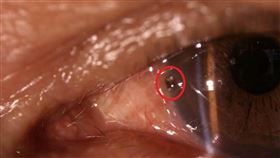

遠距問診!成功夾出老農眼球內鐵屑!

台東縣成功鎮1名50多歲農民眼睛疼痛,透過遠距醫療儀...

2019/11/29 14:44